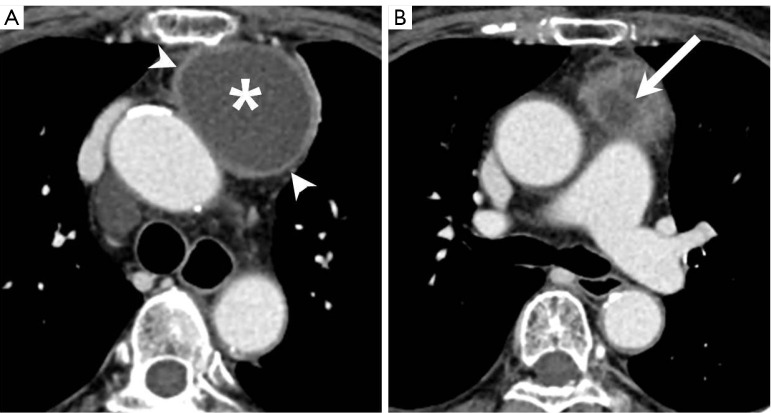

Case description: A 60-year-old woman visited Inje University Sanggye Paik Hospital with left hilar bulging detected on routine chest radiograph. A chest computed tomography (CT) scan revealed a 6 cm well-defined cystic mass with partial septation in the prevascular mediastinum. Thus, secondary thymic cyst was suggested. On the follow-up chest CT scan taken 3 months later, the size of the thymic cyst decreased, while the solid portion increased slightly, suggesting the potential presence of malignancy. Consequently, surgery was conducted. Adhesion to the lung and aorta was observed, but they were relatively well separated. The pathological findings revealed a partially ruptured thymic cyst with fat necrosis and multifocal granulomas.